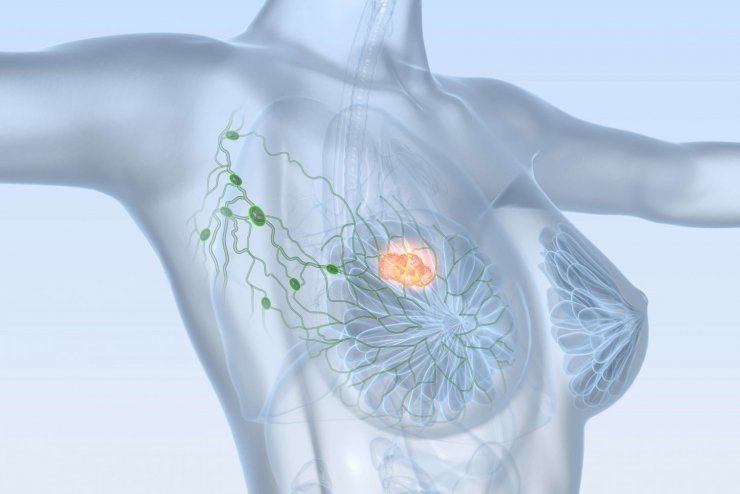

Die American Society of Clinical Oncology (ASCO) und das College of American Pathologists (CAP) haben ihre wichtigsten gemeinsamen Empfehlungen zu ER- und Progesteronrezeptor(PgR)-Tests im Rahmen ihrer Brustkrebsleitlinie aktualisiert.